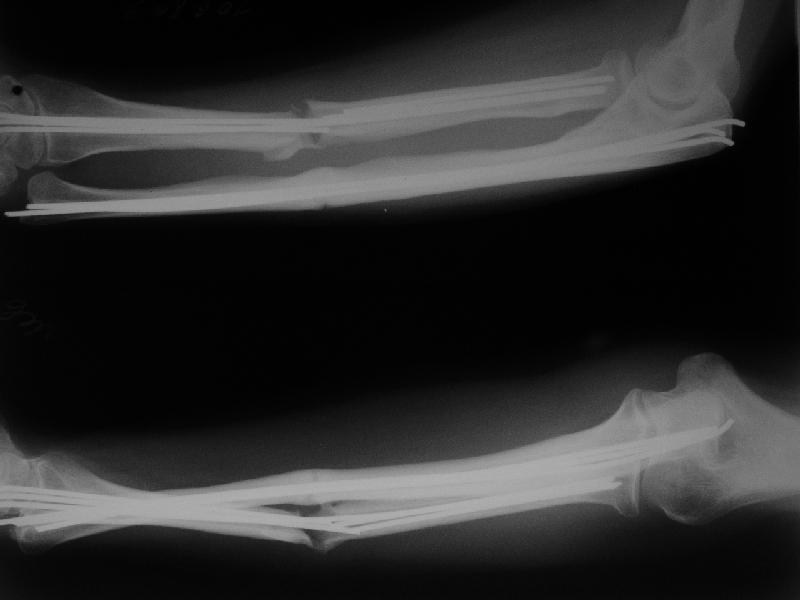

Несращение предплечья

Госпитализирована женщина, 31 год. Травма 26.09.06. Бытовая, упала. Оперирована в одной из горбольниц открыто, пучками спиц. 1 месяц в гипсе.

Подвижность усилилась примерно в 2 мес. (видимо, перелом спиц в лучевой кости). Движения в локтевом суставе N, ротация хорошая (подвижность лучевой кости), в кистевом тыльная 5-10 гр, ладонная 30 гр.

Обсуждаем варианты реостеосинтеза. Спицы удаляем все, при удалении из центрального отломка лучевой без вскрытия кости в области перелома не обойтись.

Если восстановить ось и длину лучевой кости, получается дефект ~1,5-2 см. Замещать дефект удлинением одого из отломков в аппарате? Долго, и функция кисти и пальцев может еще ухудшиться. Поэтому думаем про укорачивающую резекцию обеих костей, локтевой чуть больше, остеосинтез пластинами, наверно, LCP. Блокируемый интрамедуллярный остеосинтез тоже доступен, но есть ли тут у него преимущества?

Или есть смысл попытаться не трогать локтевую, а заместить дефект лучевой аутотрансплантатом из крыла? Или резецировать головку локтевой? Какие вариант и почему тут предпочтителен, на Ваш взгляд?